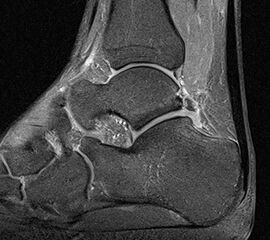

MRT

Die Kernspintomographie hat ihre Stärke in der Darstellung von Weichteilverletzungen. Insbesondere Verletzungen der Wachstumsfuge, des Periosts und der Bänder lassen sich gut visualisieren. Nachteilig ist die Untersuchungsdauer von 20-30 Minuten. Bleibt das Kind während dieser Zeit nicht ruhig liegen, kommt es zu Bewegungsartefakten, welche die Beurteilbarkeit der Bilder beeinträchtigen.

Fugengelenkfrakturen treten typischerweise vor dem 10. Lebensjahr auf, in einer Phase, in welcher die Wachstumsfugen noch weit offen sind. Dieser Frakturtyp betrifft fast ausschließlich den medialen Malleolus. Laterale Frakturen sind extrem selten, teilweise kommt es zu lateralen Bandverletzungen oder Fugenschaftfrakturen der distalen Fibula. Die Frakturlinie verläuft in einer Verlängerungslinie von der medialen Taluskante nach proximal. Häufig stellen sich Verletzungen des Innenknöchels im Röntgenbild schlechter dar, insbesondere wenn die Aufnahmen verdreht sind oder die Ebene der Fraktur bei geringer Dislokation verkippt zur Röntgenebene liegt. Besteht klinisch der geringste Hinweis auf eine Verletzung des Innenknöchels, muss aufgrund der Tragweite der Verletzung durch entsprechende Aufnahmen gegebenenfalls auch Schnittbildverfahren die Verletzung sicher diagnostiziert oder ausgeschlossen werden (Abb. 15).